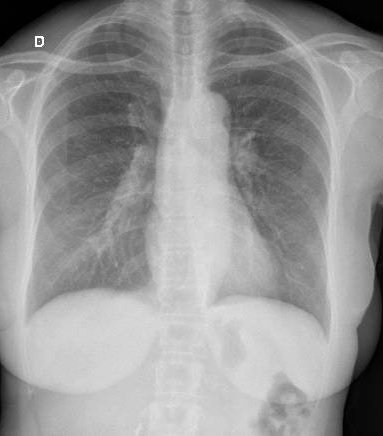

Se realizó radiografía de tórax, que mostró ensanchamiento mediastinal compatible con adenopatías hiliares, hallazgo confirmado mediante tomografía computada de tórax.

Con este cuadro clínico-radiológico se estableció el diagnóstico de síndrome de Löfgren, una forma aguda de sarcoidosis caracterizada por la tríada de eritema nodoso, artritis (habitualmente en tobillos) y adenopatías hiliares bilaterales.